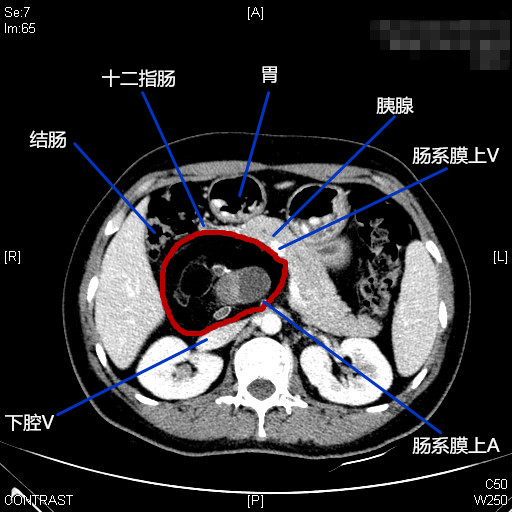

患者女性,45岁,体检发现后腹膜占位2月。CT提示:“胰腺后方可见约63*90mm混杂密度肿块影,内可见囊实性区及脂肪、牙齿,增强扫描实性区动脉期轻度强化,门脉期明显强化,边界清;腹腔干、肠系膜上动脉受压移位,考虑畸胎瘤诊断”。患者后腹膜占位诊断明确,肿瘤较大周围脏器受压,手术指征明确,拟行腹腔镜手术探查。手术困难所在:1.病变位于肝十二指肠韧带、十二指肠、胰头及横结肠后方暴露困难;2.毗邻关系复杂,病变周围与肝脏、胆囊、胆总管、横结肠、胃窦、十二指肠及胰头等重要器官毗邻;3.周围大血管多,病变与门静脉、肝总动脉、腹腔干、肠系膜动静脉、下腔静脉及左肾静脉关系密切,易导致术中大出血;4.病变系囊实性肿块牵引提拉困难。今经过团队两个小时的努力顺利切除肿瘤,术中出血约100ml。感谢麻醉师、护士及团队的辛勤付出,祝患者早日康复。